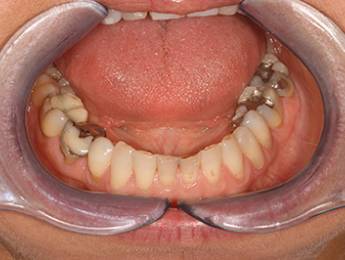

3. eset

4 implantátumra rögzített stéggel stabilizált "Overdenture" megoldás. Költséghatékony módszer fogsorok rögzítésére. Nagyfokú stabilitás érhető el redukált felületeken. Ebben az esetben jól látható, hogy a szájpadlást nem fedi be a kivehető fogsor, az ízlelés is megmarad, mégis javul a rágási képesség és a fogsorok mozgásmentesen rögzülnek.